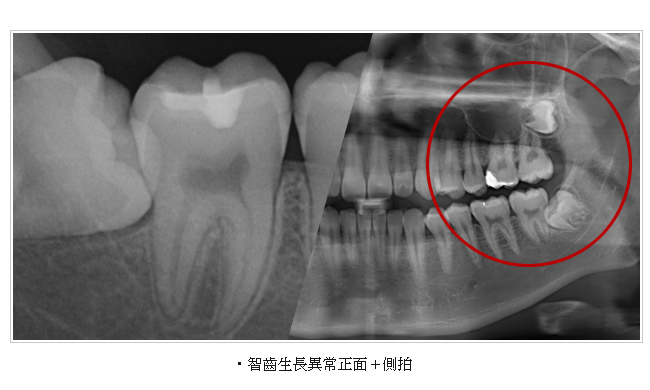

牙科專用的電腦斷層(Computed Tomography 簡稱CT)和一般的醫療電腦斷層的不同在於傳統牙科X光攝影所得的平面影像受到組織重疊的影響,無法觀察到內部的實際狀況,醫師常常因此造成誤判,為解決此問題,就需要牙科專用的3D電腦斷層攝影;若與傳統醫療電腦斷層相比較,牙科3D電腦斷層攝影有很多優點,如輻射劑量只有一般電腦斷層的1/50;採站姿或坐姿攝影,方便行動不便的患者;切片厚度一般醫療電腦斷層是 2.0 公厘,牙科3D電腦斷層則只有0.1公厘,解析度之高,比起一般醫療電腦斷層,影像當然來得細緻和精確。